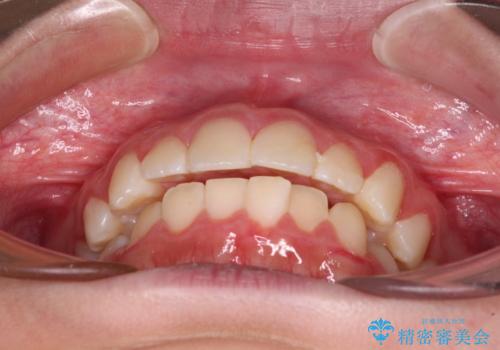

- 口元の突出感で口が閉じにくいとのことで来院された患者様です。

上下左右の第一小臼歯4本を抜歯し、ワイヤー装置での抜歯矯正を行うこととしました。

右側の咬み合わせは、上顎がやや前方位にある状態であったので、通常は補助装置を併用するのですが、高校生ということで補助装置なしで治療を行うこととしました。

口元の突出感が解消され、睡眠時の口呼吸が改善されました。